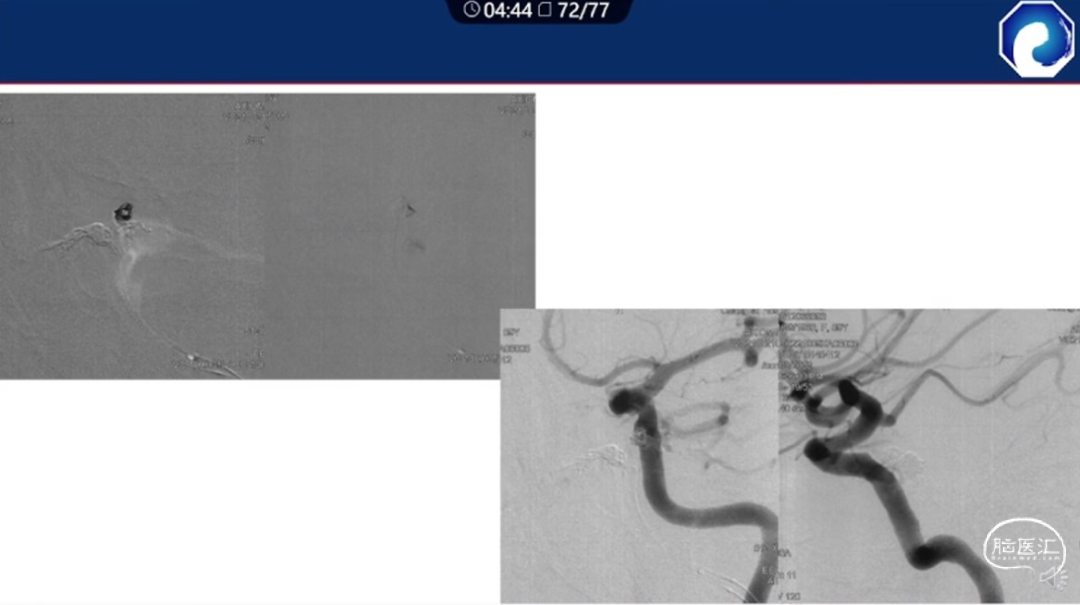

痿口静脉端精准完全闭塞是DAVF治愈的关键。

靶向性栓塞可以减少海绵窦分隔的过渡栓塞,有利于减少颅神经并发症,恢复海绵窦的正常引流功能。

减少栓塞材料应用。

减少与颈内动脉重叠,避免栓塞材料意外栓塞。